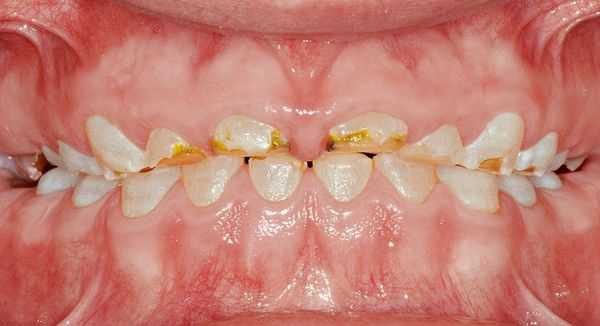

Гипоплазия эмали - недостаточное развитие поверхностного слоя (эмали) молочных или постоянных зубов. Крайне выраженной формой гипоплазии эмали является аплазия - ее полное отсутствие. Проявляется изменением формы и внешнего вида зубов, наличием белесых или депигментированных участков, бороздок, углублений, при аплазии - болевыми ощущениями на различные раздражители. Наиболее часто гипоплазия эмали ведет к развитию глубокого кариеса, пульпита, формированию неправильного прикуса.

Гипоплазия — это порок развития твёрдых тканей одного или целой группы зубов [13] . Бывает врождённым и приобретённым. Развивается тогда, когда формируются зачатки молочных или постоянных зубов. Не является кариозным поражением.

Сопровождается гипоплазия неоднородным цветом эмали, её истончением и изменением рельефа — углублениями различной формы и величины (от точек до бороздок и ямок). При прорезывании зубы сразу отличаются: на их поверхности присутствуют белые, жёлтые или коричневые пятна.

Симптомы гипоплазии зубов

То, как проявит себя гипоплазия, зависит от тяжести причинного фактора:

- при слабо выраженных нарушениях метаболизма образуются только меловидные (белые) пятна;

- при тяжёлых заболеваниях возникают серьёзные нарушения, вплоть до частичного или полного отсутствия эмали.